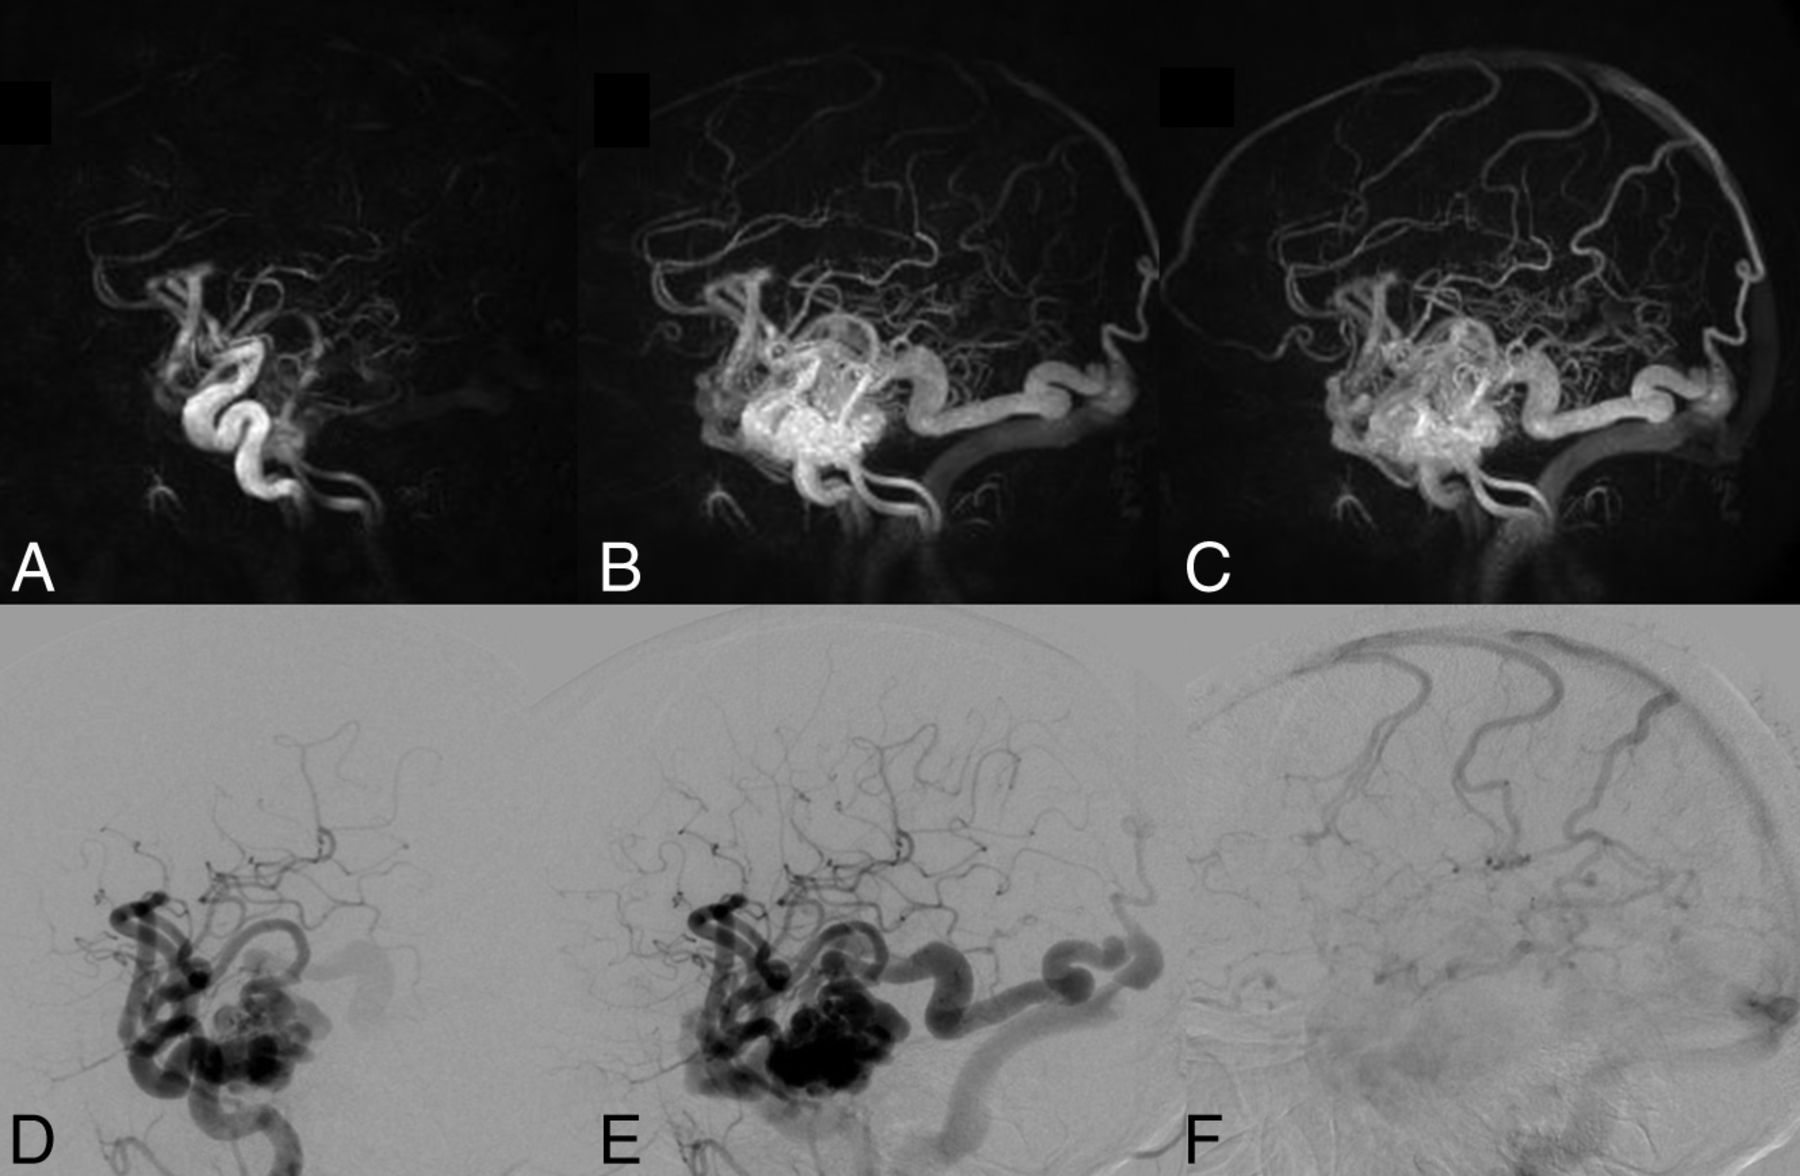

Right temporal lobe AVM. Top row: 3 HYPRFlow images from the 60-image dynamic series. Arterial (A), mixed (B), and venous phase (C) images are displayed. Bottom row: corresponding DSA arterial (D), mixed (E), and venous phase (F) images. The HYPRFlow images demonstrate the cortical venous drainage similar to the DSA.

When we compared M2/M3 arterial branches, there was no significant difference between the mean image quality scores of HYPRFlow (3.18) and TOF (3.26) (P > .05), but there were very significant differences between the image quality of both HYPRFlow and TOF compared with DSA (3.94) with P < .002 and .004, respectively. DSA deep and superficial venous image quality (3.82) was significantly better than HYPRFlow (3.08) (P < .005) (Figs 2⇓–4).